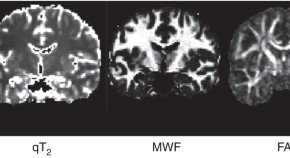

• The study of neuroanatomy using MRI enables key insights into how our brains function, are shaped by genes and environment, and how they change with development, aging and disease. The authors provide an overview of the methods for measuring the brain and also describe key artifacts and confounds

• Jason P Lerch

• André J W van der Kouwe

• Stamatios N Sotiropoulos

Review Article